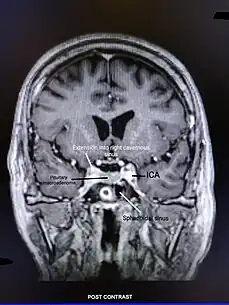

An adrenal crisis can be caused by adrenal insufficiency. Adrenal insufficiency can be classified into primary adrenal insufficiency caused by conditions affecting the adrenal cortex, secondary adrenal insufficiency due to ACTH deficiency caused by conditions affecting the hypothalamus or pituitary gland, or tertiary adrenal insufficiency caused by excessive glucocorticoid exposure. Adrenal insufficiency can be caused by autoimmune disorders such as autoimmune adrenalitis, autoimmune polyglandular syndrome, and lymphocytic hypophysitis, or congenital disorders such as congenital adrenal hyperplasia, adrenoleukodystrophy, familial glucocorticoid deficiency, combined pituitary hormone deficiency, and POMC mutation. Adrenal insufficiency can also be caused by pituitary or adrenal gland surgeries. Infections such as tuberculosis, histoplasmosis, HIV, and CMV can also cause adrenal insufficiency. Infiltrative disorders like sarcoidosis, amyloidosis, and haemochromatosis have also been known to cause adrenal insufficiency. Hemorrhages in the pituitary and adrenal glands, Waterhouse–Friderichsen syndrome, vasculitis, pituitary apoplexy, and Sheehan's syndrome are vascular disorders that can cause adrenal insufficiency. Tumors on the pituitary gland or cancer metastasis can also cause adrenal insufficiency.[10]